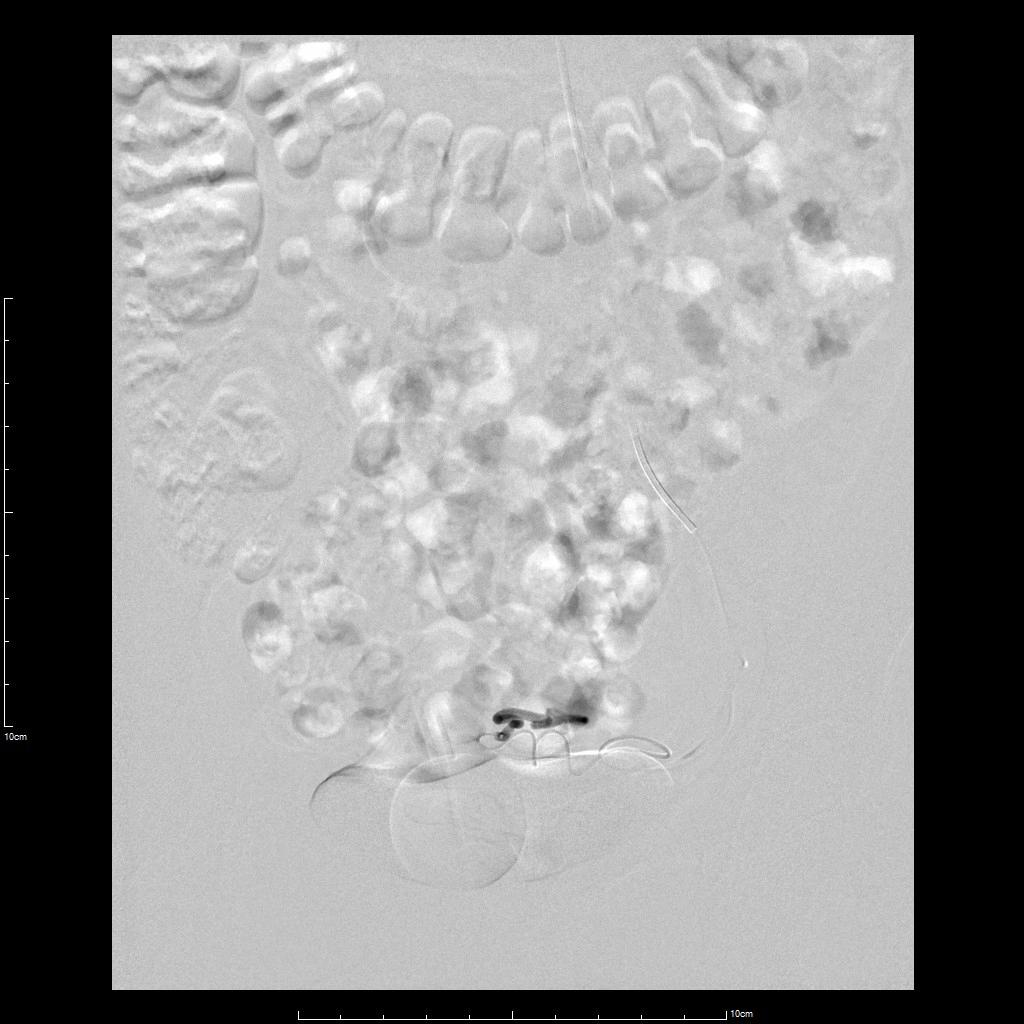

中年女性,痛经10余年,近3个月明显加重。痛经达重度疼痛,严重影响生活质量。磁共振检查显示子宫前壁囊性病灶。临床诊断为囊性子宫腺肌症。

- 经左侧桡动脉穿刺置管,行腹主动脉造影显示双侧子宫动脉增粗、迂曲。

- 超选择插管右侧子宫动脉病灶供血动脉造影+栓塞治疗。

- 超选择插管左侧子宫动脉病灶供血动脉造影+栓塞治疗。